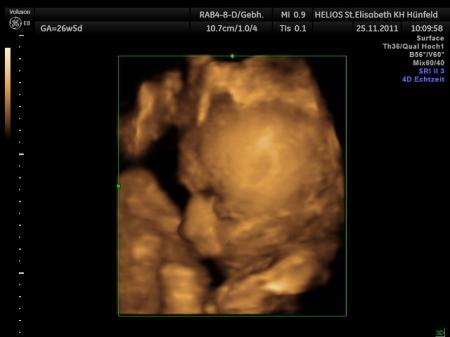

Hallo meine Lieben Daaaanke für eure Däumchen....Sie haben Glück gebracht. GMH "länger geht es nicht" O-Ton der Ärztin . Eisenwert super. Fruchtwassermenge ok, Plazenta auch einwandfrei. Zuckerfrühwerte mau, werde ab Freitag wohl abends Insulin pieken müssen...aber ok. Ich habe mittlerweile auch 4,5 kg abgenommen....das soll natürlich nicht wirklich sein. Habe auch die Rhesuspieke bekommen. Der Kleine liegt brav mit dem Köpfchen unten. Ein 3 oder 4D Bild war leider nicht möglich, er hat immer die Füßchen und Händchen aus dem Bild gezogen und seine Hand vor die Augen gelegt...Schlingel . Freitag hab ich den ersten offiziellen CTG Termin....muss auf jeden Fall an ein Buch denken . Die Maße von heute: 34 cm und 1,1 kg. Er ist also "nur" noch eine Woche voraus momentan. Mann....ich bin erleichtert....uind morgen wird in die 29. SSW gerollt....einfach toll. Ganz lieben Gruß an euch Daniela

Bild zu